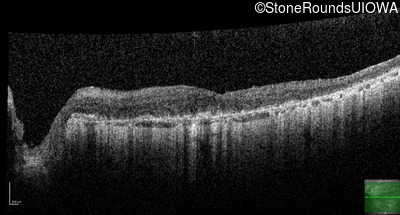

This 81 year old man began using a flashlight to read menus in his 40's. At age 75 his ophthalmologist noticed abnormal fundus findings and referred him to a retina specialist.

| Age at visit: 81 years |

| Age at visit: 82 years |

| Age at visit: 83 years |

| Age at visit: 84 years |

| Age at visit: 85+ (Visit 1) |

| Age at visit: 85+ (Visit 2) |